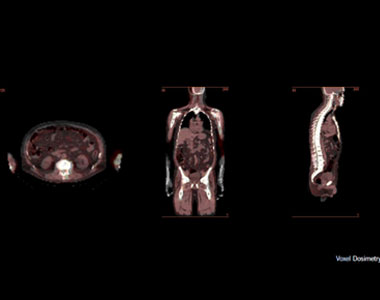

Voxel Dosimetry

One of the Hermia Dosimetry module; the Voxel Dosimetry. It Process DICOM images from all camera manufacturers using the same workflow with automatic alignment of multiple quantitative SPECT/CT or PET/CT time points. Cumulated activity in each voxel is calculated and a Monte Carlo algorithm simulates photon absorption and scatter through the patient’s CT to calculate dose distribution over the entire field of view. Dose-volume histogram analysis is available to provide a detailed understanding of dose distribution in volumes of interest. Store dose maps as DICOM for further and future analysis.